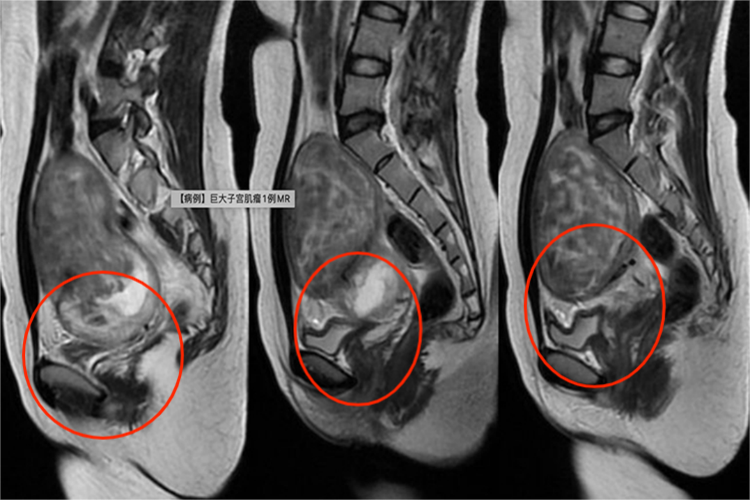

子宫肌瘤压迫膀胱可出现压迫症状,子宫前壁下段肌瘤可压迫膀胱引起尿频;宫颈肌瘤可引起排尿困难、尿潴留;子宫后壁肌瘤可引起便秘等症状。较大肌瘤可在下腹部扪及实质性肿块,子宫增大,表面不规则单个或多个结节状突起。黏膜下肌瘤位于宫腔内者子宫均匀增大,脱出于宫颈外口者,宫颈口处有肿物,粉红色,表面光滑,宫颈外口边缘清楚。若伴感染时可有坏死、出血及脓性分泌物。

子宫肌瘤患者可使用雄激素对抗雌激素,使子宫内膜萎缩,还可使用促性腺激素释放激素类似物,降低雌激素至绝经后水平。子宫肌瘤体积大或引起膀胱、直肠等压迫症状,需手术治疗,可采取经腹或经腹腔镜子宫肌瘤剔除术、经阴道黏膜下肌瘤扭除术等。